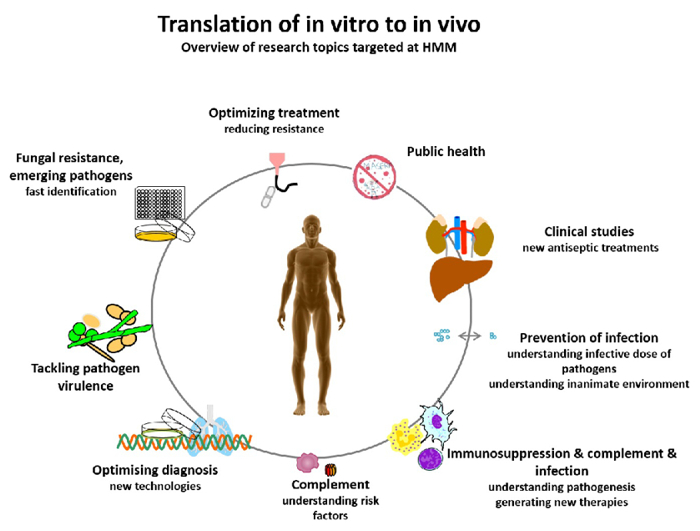

- HMM seeks to prevent illness and death from targeted infectious disease threats through research and the translation of scientific information into real-world, practical applications, policies, and solutions (Fig. 1).

Infectious diseases are becoming one of the most frequent causes of death in the world; at present, we face bacteria and fungi that are developing resistance to antibiotics and antimycotics as well as the fact that an increasing number of emerging pathogens are spreading worldwide. Understanding the biological principles underlying the mechanisms by which infectious agents adapt and undermine the defence mechanisms of a host is critical to fighting diseases. HMM conducts basic and translational research into molecular mechanisms of pathogenesis of bacterial, viral, or fungal infections and strategies for prophylaxis and treatment. HMM’s mission is to coordinate and strategically align translational infection research with the aim of developing new diagnostic, preventive and therapeutic methods to treat infectious diseases. To achieve this, HMM has formed thematic translational units of scientists, each dedicated to one specific pathogen or infectious disease. HMM is one of the largest diagnostic microbiology laboratories in Austria and has an average sample throughput of 250,000 specimens per year. It is associated with all the major hospitals in Tyrol, and therefore holds a key position in the diagnostic laboratory landscape of Austria. The working groups of Reinhard Würzner, Doris Wilflingseder and Wilfried Posch cover the topic “Exploiting immune response”, the working groups of Michaela Lackner and Cornelia Lass-Flörl with Cornelia Speth and Ulrike Binder investigate fungal infections. “N-chlorotaurin” is the main research focus of Markus Nagl, and Peter Kreidl covers the topic of public health. Astrid Mayr is connected with the CD Laboratory. The mission of HMM is to bridge the gap between basic and translational research into microbial pathogenesis (Fig. 2).